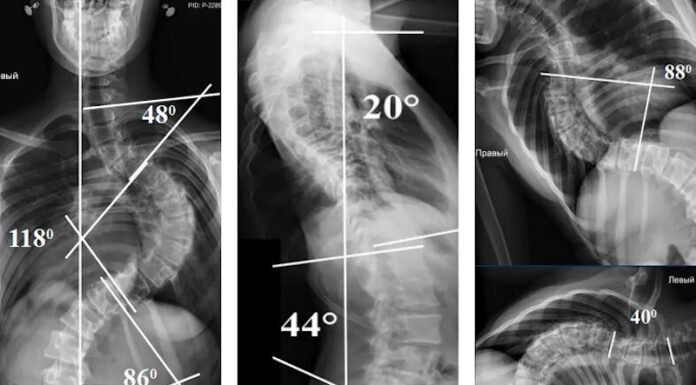

Виявлений сколіоз? Шукаєте найкращих спеціалістів для операції? Хочемо представити клінічний приклад, виконаний у нашому Інституті експертною командою хірургів у складі к.м.н. Баркова О.О., к.м.н. Чернишова О.Г., к.м.н. Баєва В.В., к.м.н. Палкіна О.В.

Пацієнтка М., 14 років, поступила в клініку патології хребта дитячого віку з діагнозом: Ідіопатичний правобічний грудний сколіоз IV ступеня (тип 3AN по Lenke).

У зв’язку з великою та...